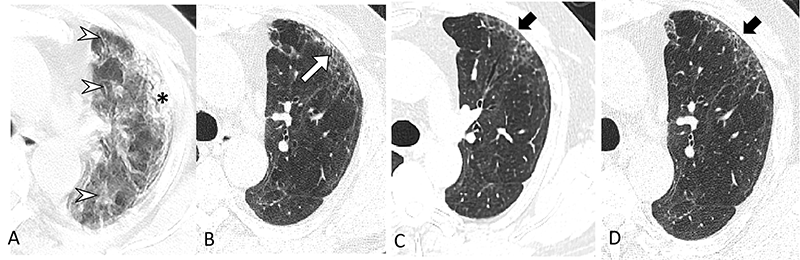

Serial transverse CT scans in a 65-year-old man with severe COVID-19. (A) CT scan obtained on day 23 after onset of symptoms showed diffuse ground-glass opacities (arrow heads) combined with subpleural consolidation (*) at the left upper lobe. (B) Image obtained at 6-month follow up showed subpleural primarily ground-glass opacity in the anterior upper lobe of the left lung along with minor bronchiectasis (white arrow). (C, D) Images obtained at 12-month and 2-year follow up showed presence of subtle, subpleural honeycombing at the same area (black arrows). This patient complained of ongoing exertional dyspnea and showed a mild diffusing capacity of the lung for carbon monoxide (74%) at 2-year follow up.

Over two years, the incidence of lung abnormalities gradually decreased. At six months, 54% of patients showed lung abnormalities. On two-year follow-up CT scans, 39% (56/144) of the patients had lung abnormalities, including 23% (33/144) with fibrotic lung abnormalities and 16% (23/144) with non-fibrotic lung abnormalities.

“In particular, the proportion of fibrotic interstitial lung abnormalities, an important precursor to idiopathic pulmonary fibrosis, remained stable throughout follow-up,” the authors said. “Therefore, the fibrotic abnormalities observed in our study might represent a stable, irreversible pulmonary condition, such as lung fibrosis, after COVID-19.”

At two-year follow-up, the most common respiratory symptom was exertional dyspnea (14% [20/144]), while mild and moderate pulmonary diffusion were observed in 29% (38/129) of patients. Pulmonary diffusion was regarded as abnormal when diffusing capacity of the lung for carbon monoxide was less than 75% of the predicted value. The researchers suggest that persisting residual symptoms and abnormal lung function could be related to the patient’s ongoing lung damage.